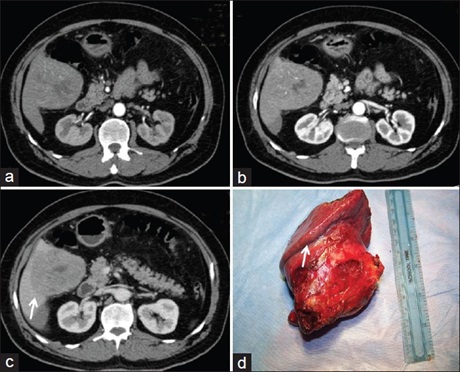

Preoperative diagnosis of the organ of origin in cases of exophytic lesions of liver is difficult and a challenge for the radiologist and clinicians. It needs careful examination and interpretation of radiological findings for correct diagnosis. We present our experience with exophytic liver lesions in four patients diagnosed with hepatocellular adenoma, hepatocellular carcinoma (HCC), cavernous hemangioma, and hydatid cyst, and highlighted these issues.